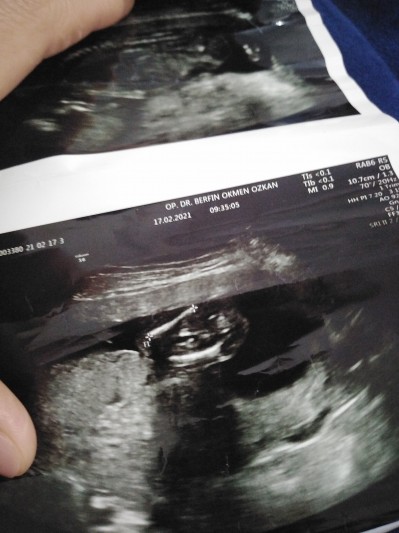

image

15 hafta

15.haftada nub olmaz 11 12 13 haftalar olmali tahmin icin

Kıza benziyor dedi ama keseye göre tahmin almak istedim

Kız bebiş nerde ben göremedim :Dbacak falan gördüm sanki :angel:

Ayakları karnına cekmiş gbi duruyor keseye göre felan tahmin bekliirom doktor kıza benziyor dedi